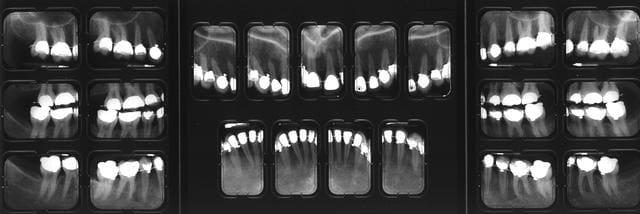

mes radios, à J + 3 mois...

(ben quoi? je vérifie le boulot de l'autre ;-))

Mr le radiologue (Gérard Pasquet de son nom, vous savez le Mr du bouquin de radiologie :-)) s'inquiète pour ma 31/ trouve que j'ai une image apicale au bout...moi pas trop...

Vous en pensez quoi?

et puis regardez ma 21, comme elle aime pas tout ce qu'elle subit :-((((